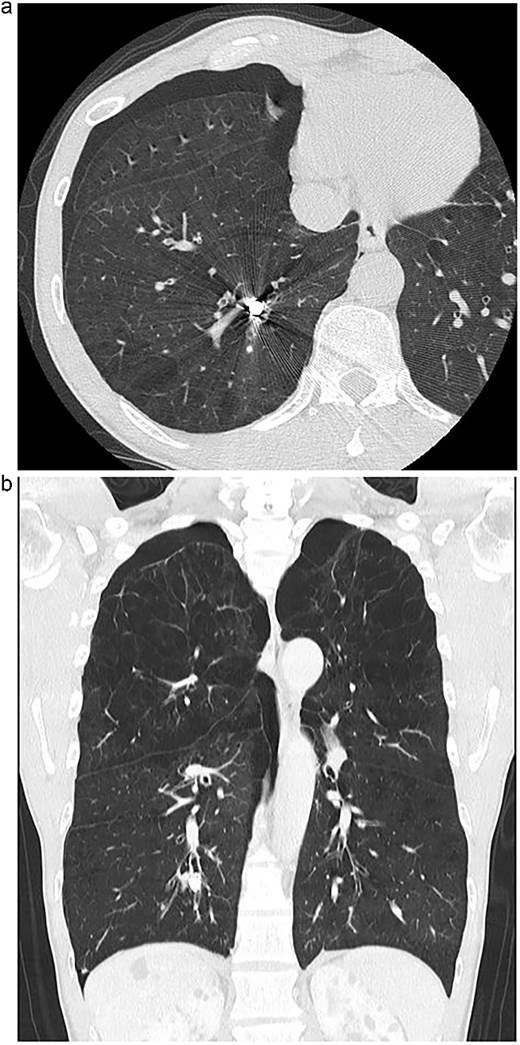

An 82-year-old man presented with chronic cough and a history of repeated right-sided pneumonia. Chest computed tomography (CT) showed a high-density object located in the posterior basal segment (S10) of the right lower lobe (Fig. 1a and b). Bronchoscopy revealed a dental prosthesis impacted in the B10b+c bronchus with surrounding granulation tissue (Fig. 2a). Removal via flexible bronchoscopy was unsuccessful due to firm impaction.

(a) Axial chest CT showing a high-density foreign body in the right S10 bronchus. (b) Coronal CT confirming the position of the dental prosthesis in the posterior basal segment.